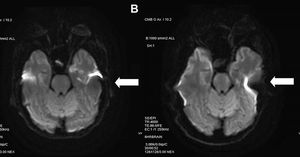

Importance of phase direction selection on #DWI: Phase direction (A) AP and (B) RL. (A) is more symmetric. Both images were acquired at 3 T field strength. #MRI